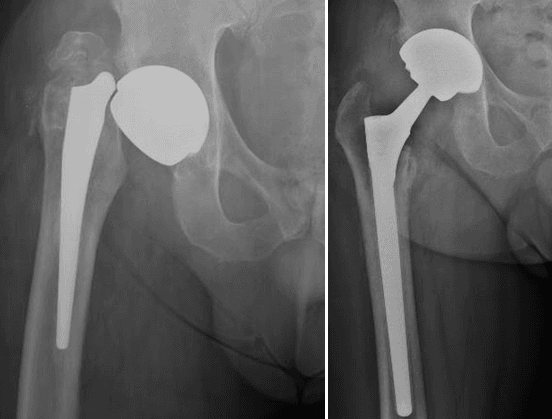

L’intervento chirurgico di revisione protesica si attua nel caso di fallimento dell’impianto primario. La revisione può essere totale (quando vengono sostituite tutte le componenti) o parziale (quando vengono sostituite solo alcune componenti), a seconda dell’entità e del tipo di problema riscontrato.

La revisione protesica rappresenta una vera e propria sfida per il Chirurgo Ortopedico, soprattutto in quei casi gravati da importante perdita del bone stock, da deficit dei tessuti molli periarticolari o in presenza di alterazioni del trofismo cutaneo, talvolta con perdita severa di sostanza, in esiti di plurimi interventi chirurgici.

Grazie ad un’esperienza chirurgica decennale nel trattamento e nella gestione di casi difficili di revisione protesica, presso il nostro centro di Chirurgia Protesica pianifichiamo accuratamente gli interventi ricostruttivi protesici, avvalendoci delle più innovative tecniche e metodiche chirurgiche (impianti protesici su misura quando necessari), ponendo particolare attenzione nell’utilizzo di materiali protesici biocompatibili che garantiscono un’ottimale osteointegrazione ed una resistenza all’usura sempre maggiore.